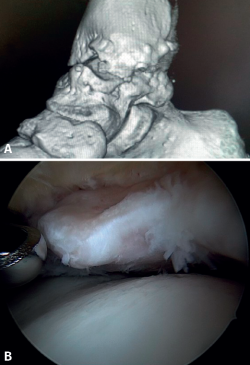

El PAT óseo por osteofitos también ha sido relacionado con la presencia de inestabilidad crónica. Se ha postulado que la alteración en la cinemática articular secundaria a la insuficiencia ligamentosa favorece el desarrollo de osteofitos en la región anterior de la tibia y el astrágalo(36,37). Estudios recientes han cuestionado la teoría de tracción capsular repetida como origen de los osteofitos en la práctica deportiva(38), ya que es fácilmente demostrable que los osteofitos se localizan intraarticulares por dentro de la inserción capsular, en el contexto de una artroscopia de tobillo (Figura 2). Por ello, la artroscopia con dorsiflexión de tobillo es fundamental para poder resecar los osteofitos de forma segura sin daño capsular ni a las estructuras suprayacentes, mientras que la técnica clásica de tracción (invasiva o no) dificultaría enormemente su resección, por lo que hoy en día se desaconseja su uso rutinario(3,39). Vega distingue dos tipos de osteofitos(3), según sean por trauma repetitivo (forma de pico) o por inestabilidad (en forma de visera). El concepto de microinestabilidad se asocia a microtraumatismos de repetición que podrían ser el origen de osteofitos con esta morfología característica (Figura 3).

La resección de osteofitos se realiza deslizándose desde su parte superior, rebajando gradualmente hasta alcanzar la zona articular (Figura 2). Con una pinza de tipo basket se puede resecar la zona más cercana a la articulación (Figura 5). Suele ser útil intercambiar los portales de visión y trabajo para visualizar y resecar completamente los osteofitos. Para el pinzamiento de partes blandas, un sinoviotomo de 3,8 o 4 mm suele ser suficiente. El vaporizador es útil en pinzamientos compactos, típicos de condiciones postraumáticas o reintervenciones, también para delimitar la parte ósea del osteofito antes de su resección.

Figura 2. Osteofito anterior de la tibia. A: en dorsiflexión la cápsula se separa del osteofito permitiendo su resección (B) mediante fresado.

Figura 3. Osteofito por inestabilidad crónica. A: el osteofito conforma un tope óseo que se extiende en el borde anterior del plafón tibial y la cara anterior del maléolo medial; B: imagen artroscópica.